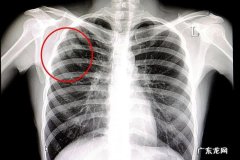

【肺结核怎样检测出来】胸片检查发现肺结核病变 。为了更准确地诊断肺结核疾病,有必要进行CT检查来诊断肺结核疾病 。CT检查可以进一步诊断肺结核病变的程度,CT检查结果可以评估疾病的严重程度,为以后的治疗提供解决方案 。